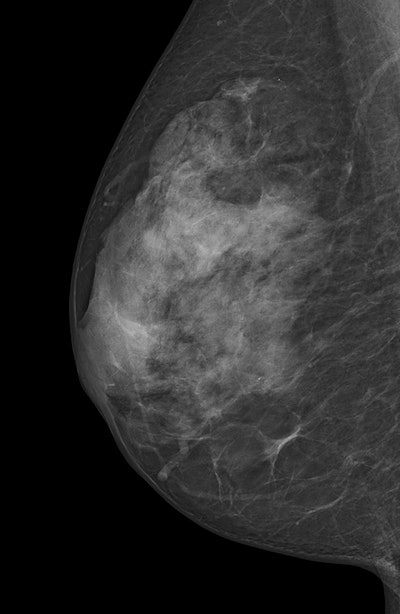

Digital mammogram of an ACR 4 dense breast."In other words, only one out two breast cancer cases occurring among screening participants with ACR 4 over a period of 24 months was detected in the screening examination," they wrote. "Most likely, a varying extent of masking and obscuring of tumor signs -- if not associated with microcalcifications or architectural distortion -- in breasts consisting of up to 75% dense tissue (ACR 3) versus over 75% dense tissue (ACR 4) might lead to such a discrepant screening performance."

Worthy of note, however, is the average sensitivity of the program in women with ACR 3, as contrasted by sensitivity in ACR 4 of only 50% -- statistically significant irrespective of the reading-related classification selected.

"The rate of breast cancers detected at screening was lower for breasts classified as ACR 4 than ACR 3 while the rate of interval cancers was higher, but these findings were not clearly significant," the authors wrote.